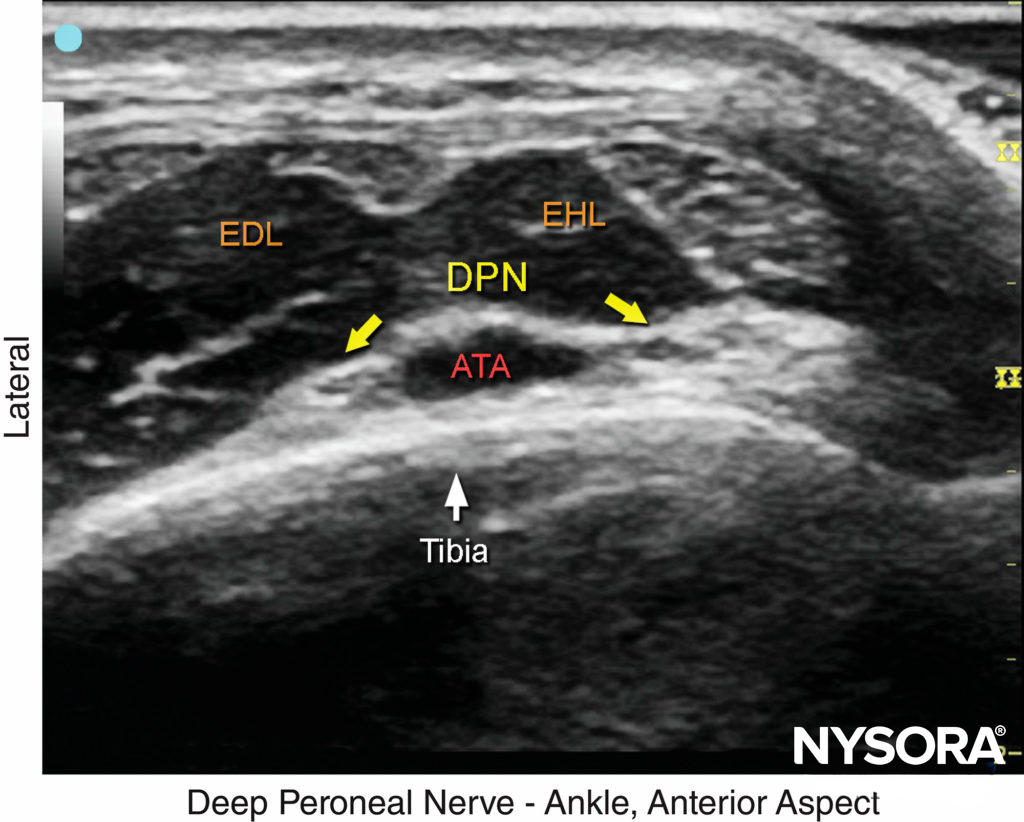

FIGURE 6. US image of the deep peroneal nerve (DPN), seen at the surface of the tibia just lateral to the anterior tibial artery (ATA). The nerve is divided in this image. The surrounding tendons are the extensor hallucis longus (EHL) and the extensor digitorum longus (EDL). (Reproduced with permission from Hadzic A: Hadzic’s Peripheral Nerve Blocks and Anatomy for Ultrasound-Guided Regional Anesthesia, 2nd ed. New York: McGraw-Hill, 2011.)

This branch of the common peroneal nerve innervates the ankle extensor muscles, the ankle joint and the web space between the first and second toes. As it approaches the ankle, the nerve crosses the anterior tibial artery from a medial to lateral position. A transducer placed in the transverse orientation at the level of the extensor retinaculum will show the nerve lying immediately lateral to the artery, on the surface of the tibia (Figures 4, 5, and 6). In some individuals the nerve courses along the medial side of the artery. The nerve usually appears hypoechoic with a hyperechoic rim, but it is small and often difficult to distinguish from the surrounding tissue.

FIGURE 5. Cross-sectional anatomy of the deep peroneal nerve at the level of the ankle. The deep peroneal nerve (DPN) is located just lateral to anterior tibial artery (ATA) and between extensor hallucis longus (EHL) and tibia. Note the proximity of the extensor digitorum longus (EDL) and the tibialis anterior (TA), which can serve as an important landmark; to locate it, flex and extend the patient’s great toe manually. The deep peroneal nerve appears divided in this section. (Reproduced with permission from Hadzic A: Hadzic’s Peripheral Nerve Blocks and Anatomy for Ultrasound-Guided Regional Anesthesia, 2nd ed. New York:McGraw-Hill, 2011.)